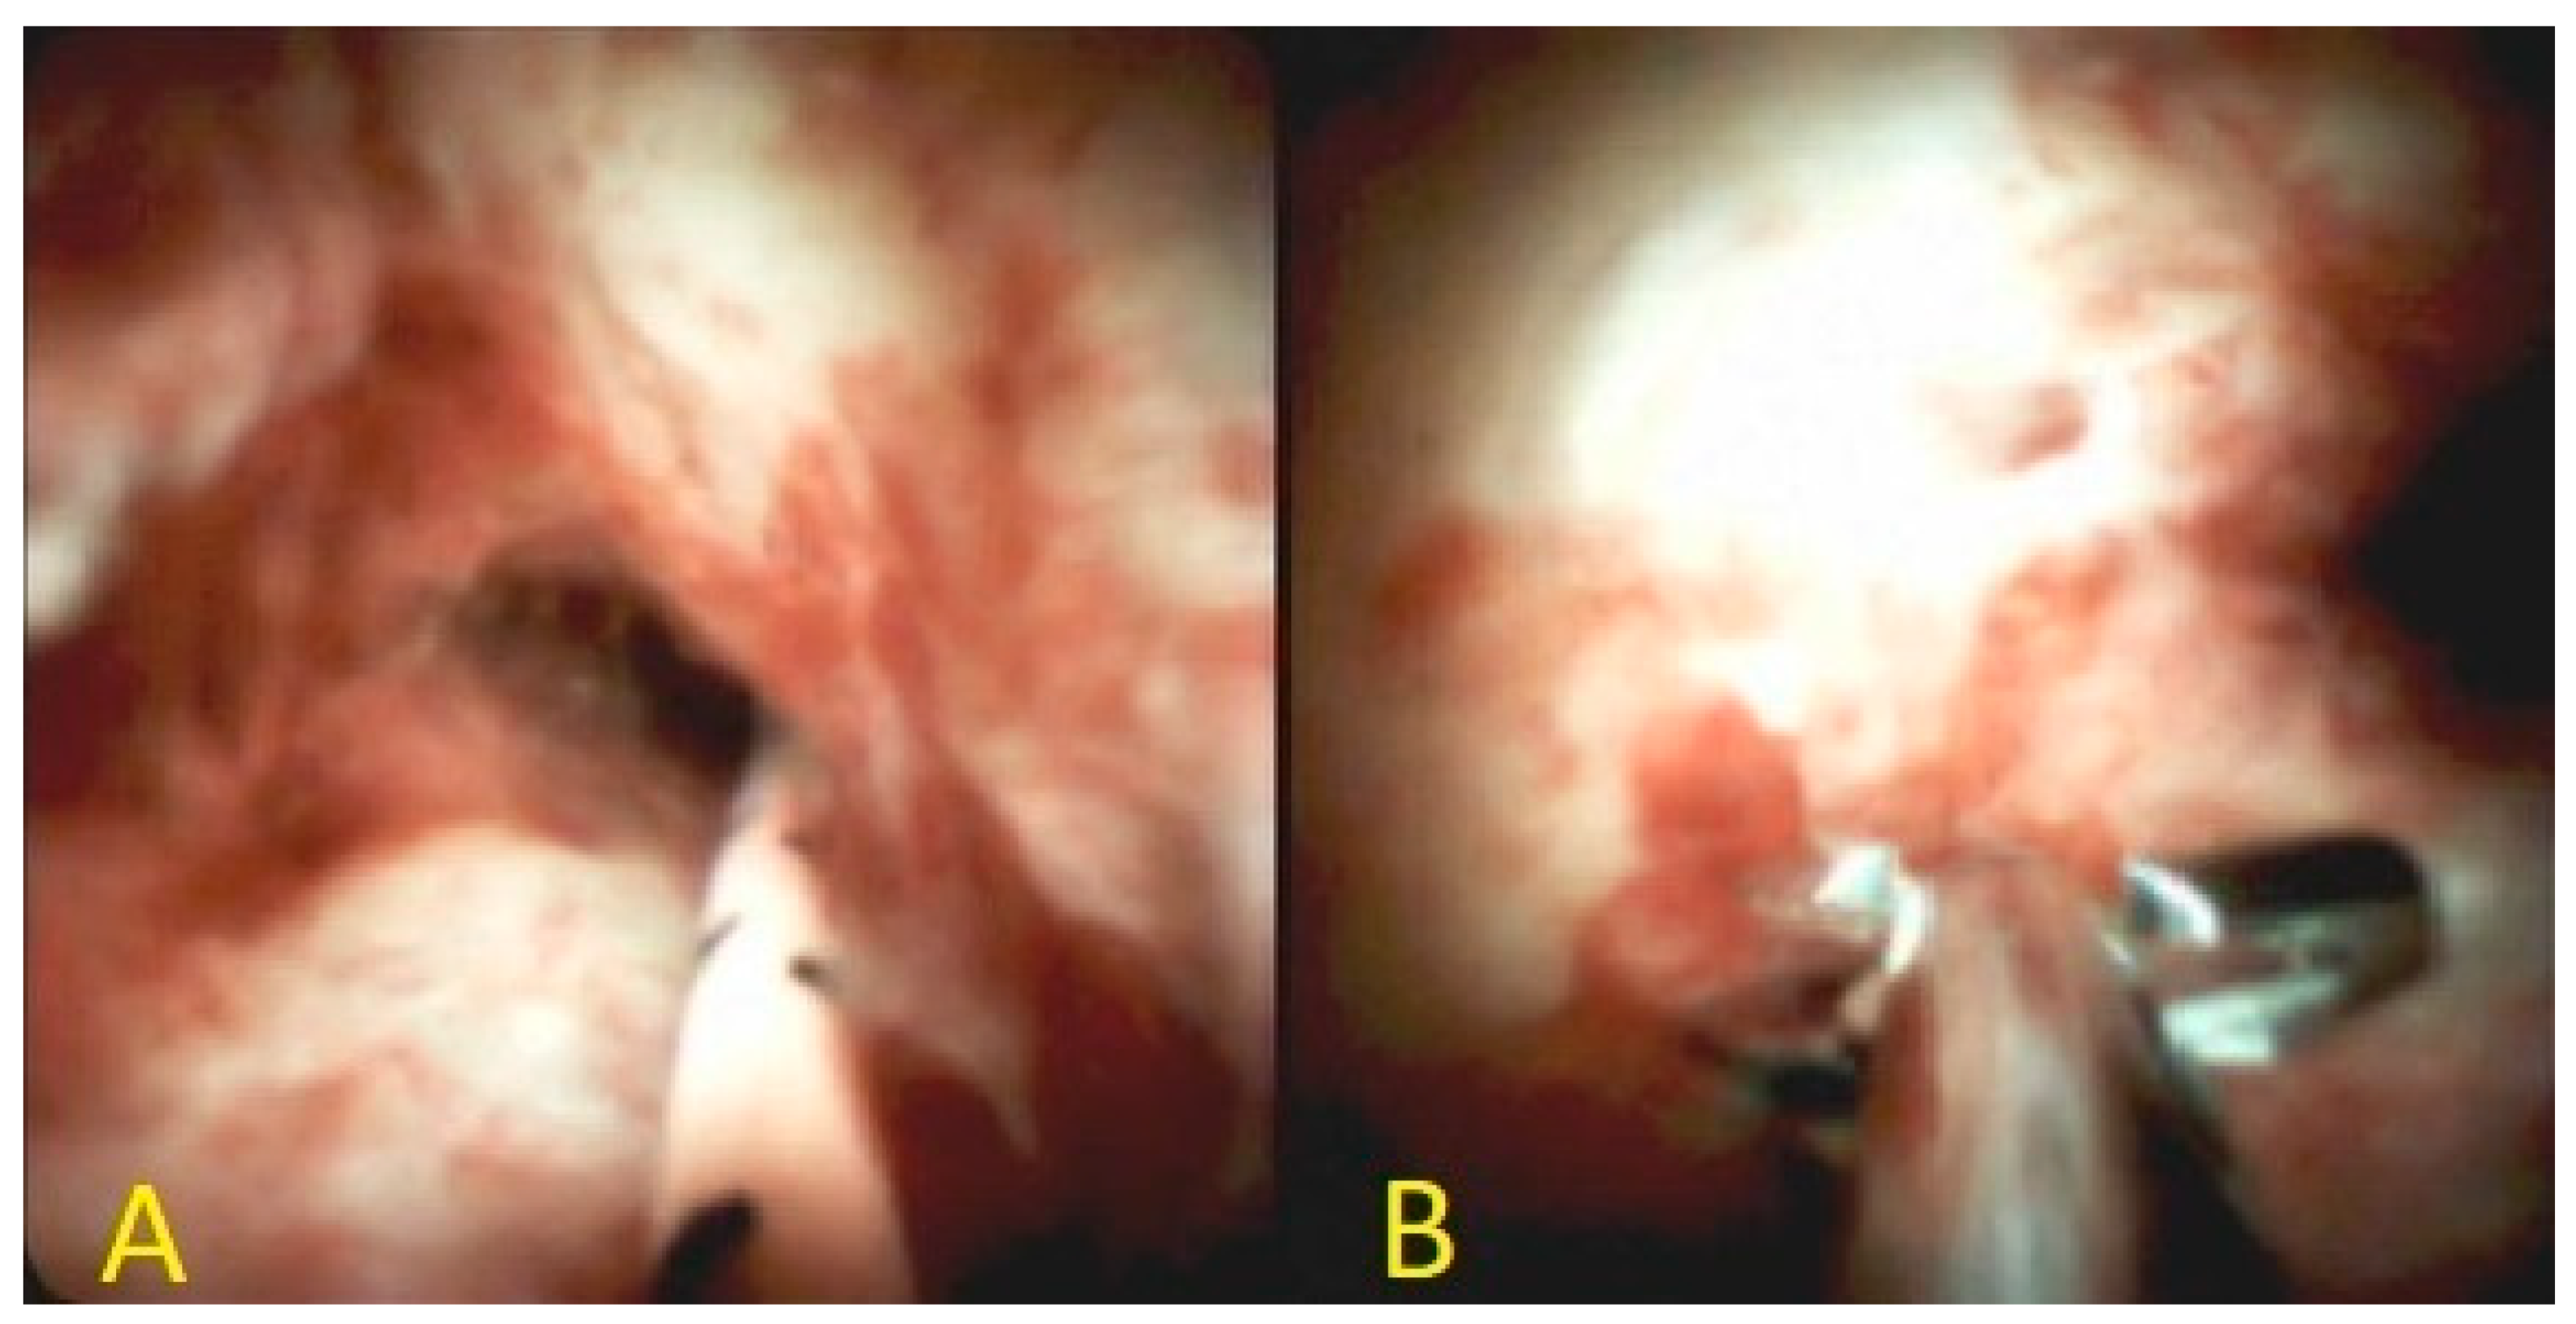

6.2. Cholangioscopy

- Ayoub, F.; Yang, D.; Draganov, P.V. Cholangioscopy in the digital era. Transl. Gastroenterol. Hepatol. 2018, 3, 82. [Google Scholar] [CrossRef] [PubMed]

- Kulpatcharapong, S.; Pittayanon, R.; Kerr, S.J.; Rerknimitr, R. Diagnostic performance of different cholangioscopes in patients with biliary strictures: A systematic review. Endoscopy 2020, 52, 174–185. [Google Scholar] [CrossRef]

- Pérez-Cuadrado-Robles, E.; Deprez, P.H. Indications for Single-Operator Cholangioscopy and Pancreatoscopy: An Expert Review. Curr. Treat. Options Gastroenterol. 2019, 17, 408–419. [Google Scholar] [CrossRef]

- Sethi, A.; Doukides, T.; Sejpal, D.V.; Pleskow, D.K.; Slivka, A.; Adler, D.G.; Shah, R.J.; Edmundowicz, S.A.; Itoi, T.; Petersen, B.T. Interobserver agreement for single operator choledochoscopy imaging: Can we do better? Diagn. Ther. Endosc. 2014, 2014, 1–4. [Google Scholar] [CrossRef]

- Sethi, A.; Tyberg, A.; Slivka, A.; Adler, D.G.; Desai, A.P.; Sejpal, D.V.; Pleskow, D.K.; Bertani, H.; Gan, S.-I.; Shah, R. Digital Single-operator Cholangioscopy (DSOC) Improves Interobserver Agreement (IOA) and Accuracy for Evaluation of Indeterminate Biliary Strictures: The Monaco Classification. J. Clin. Gastroenterol. 2020. [Google Scholar] [CrossRef]